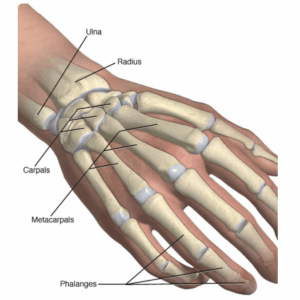

Broken hand

A broken hand occurs when one or more of the bones of your hand break or crack, often because of a fall. When falling, people reach out their hands to catch themselves. This movement is instinctive. This can lead to a break or crack, also called a fracture.

Broken wrist

A broken wrist is a break or crack in one or more of the bones of your wrist. The most common of these injuries occurs in the wrist when people try to catch themselves during a fall and land hard on an outstretched hand.